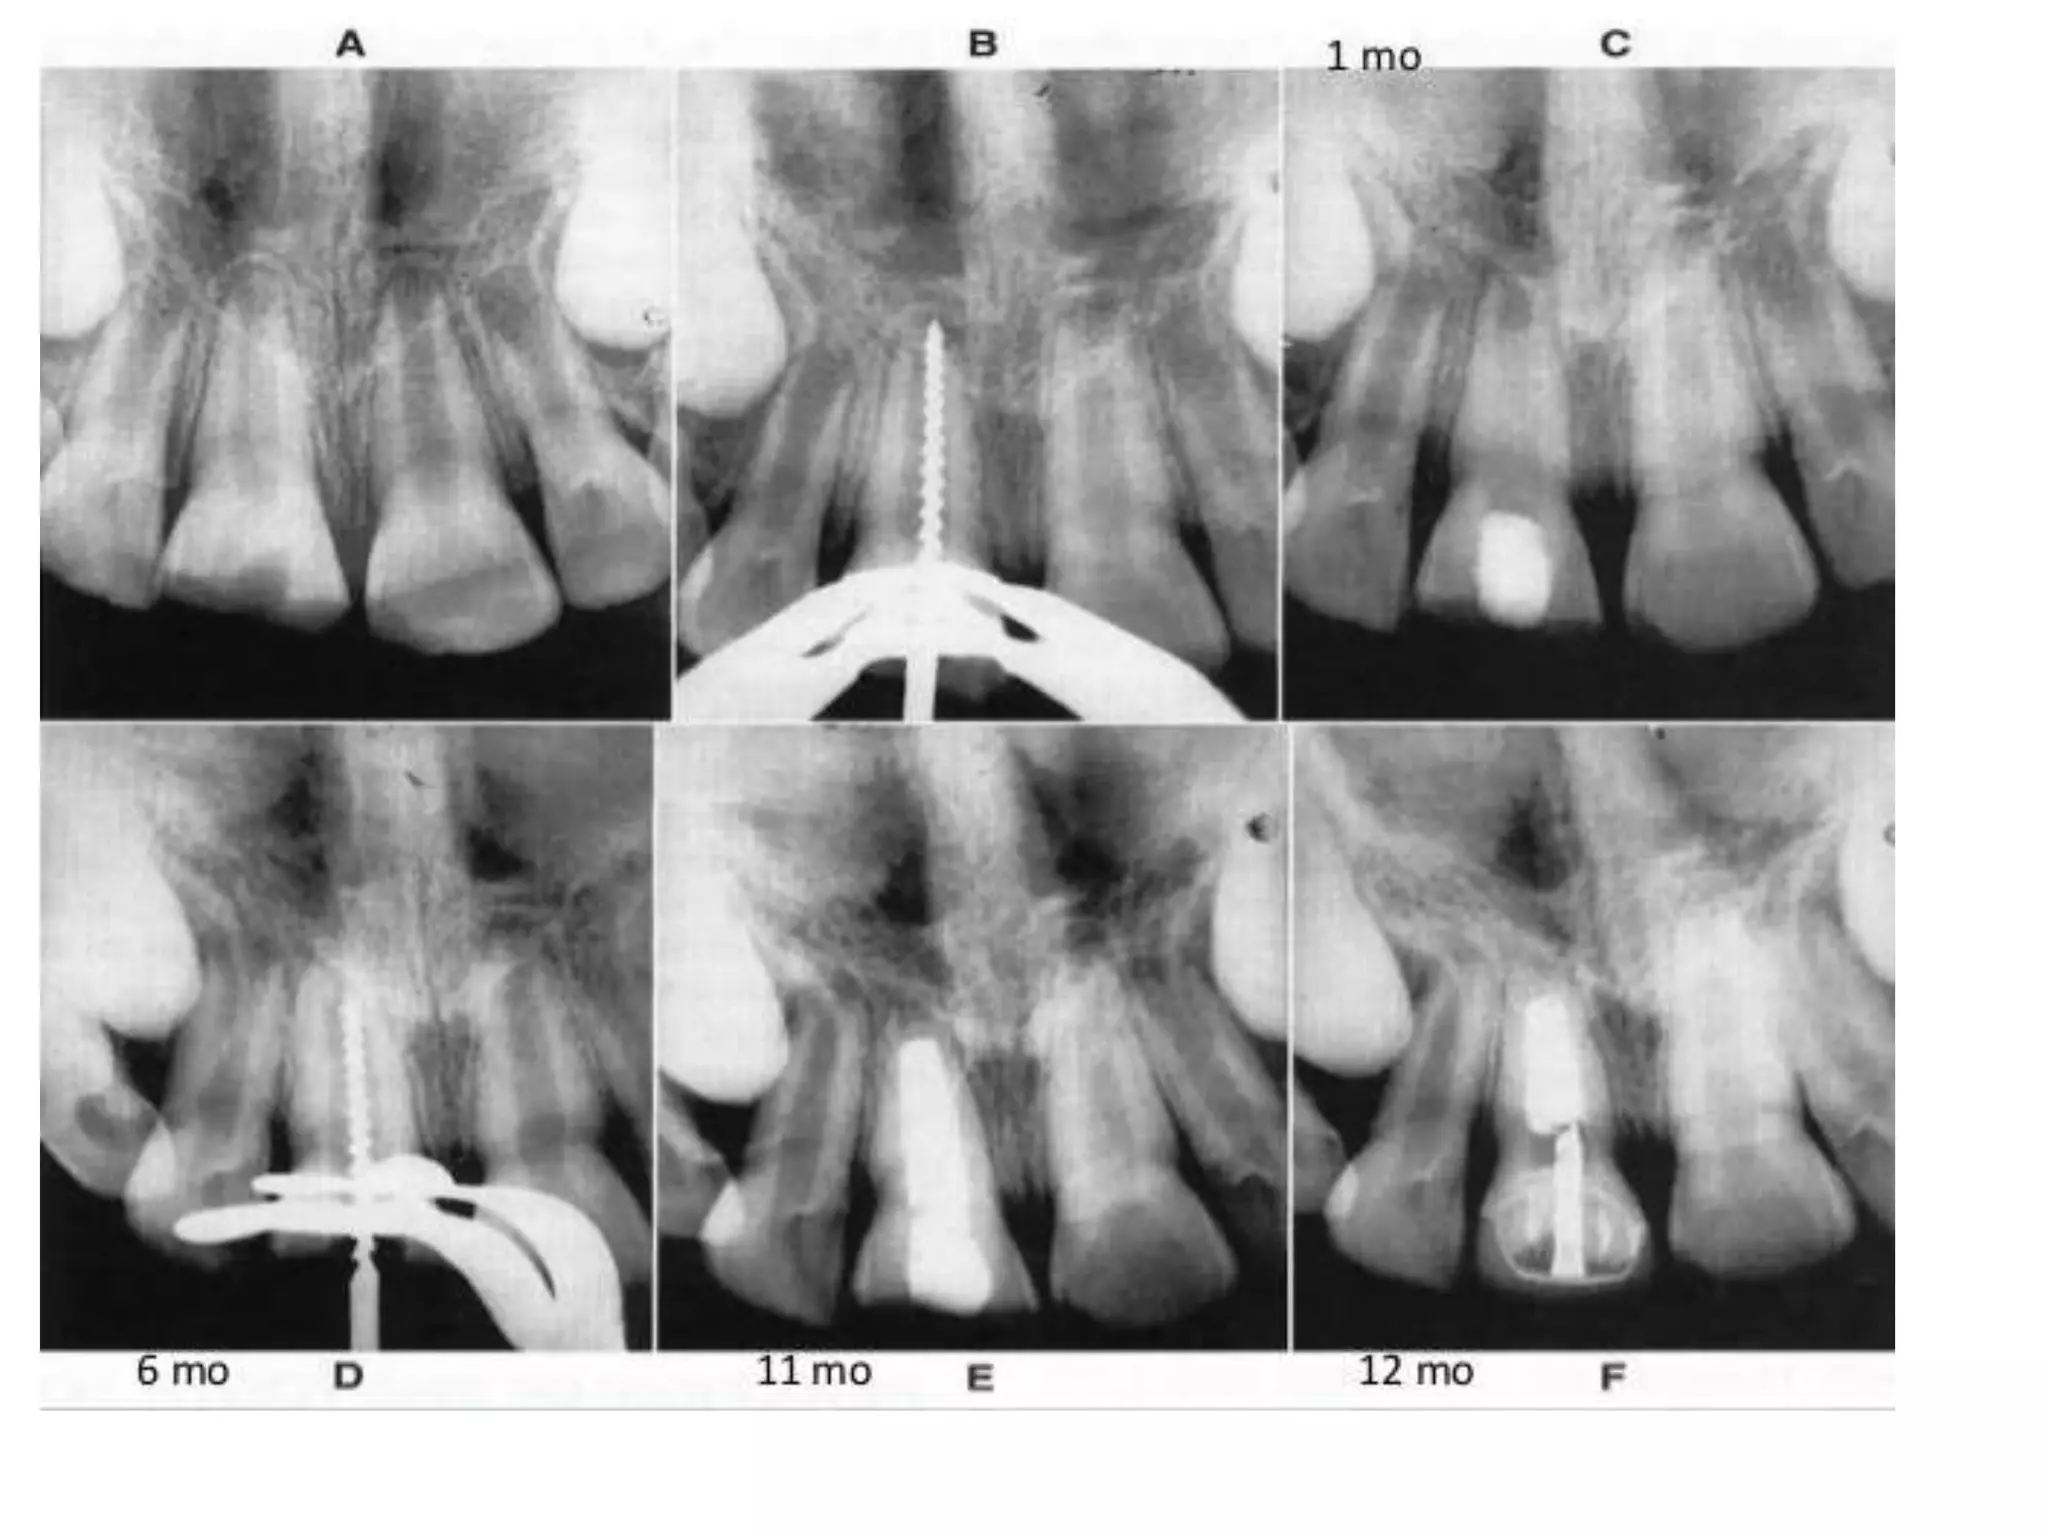

Apexogenesis and apexification are treatments relevant to the trauma of maxillary central incisors, which are frequently injured in children. The highest instance of such trauma is observed between the ages of 8 and 10. There is an exploration of new strategies for treating teeth with an open apex.